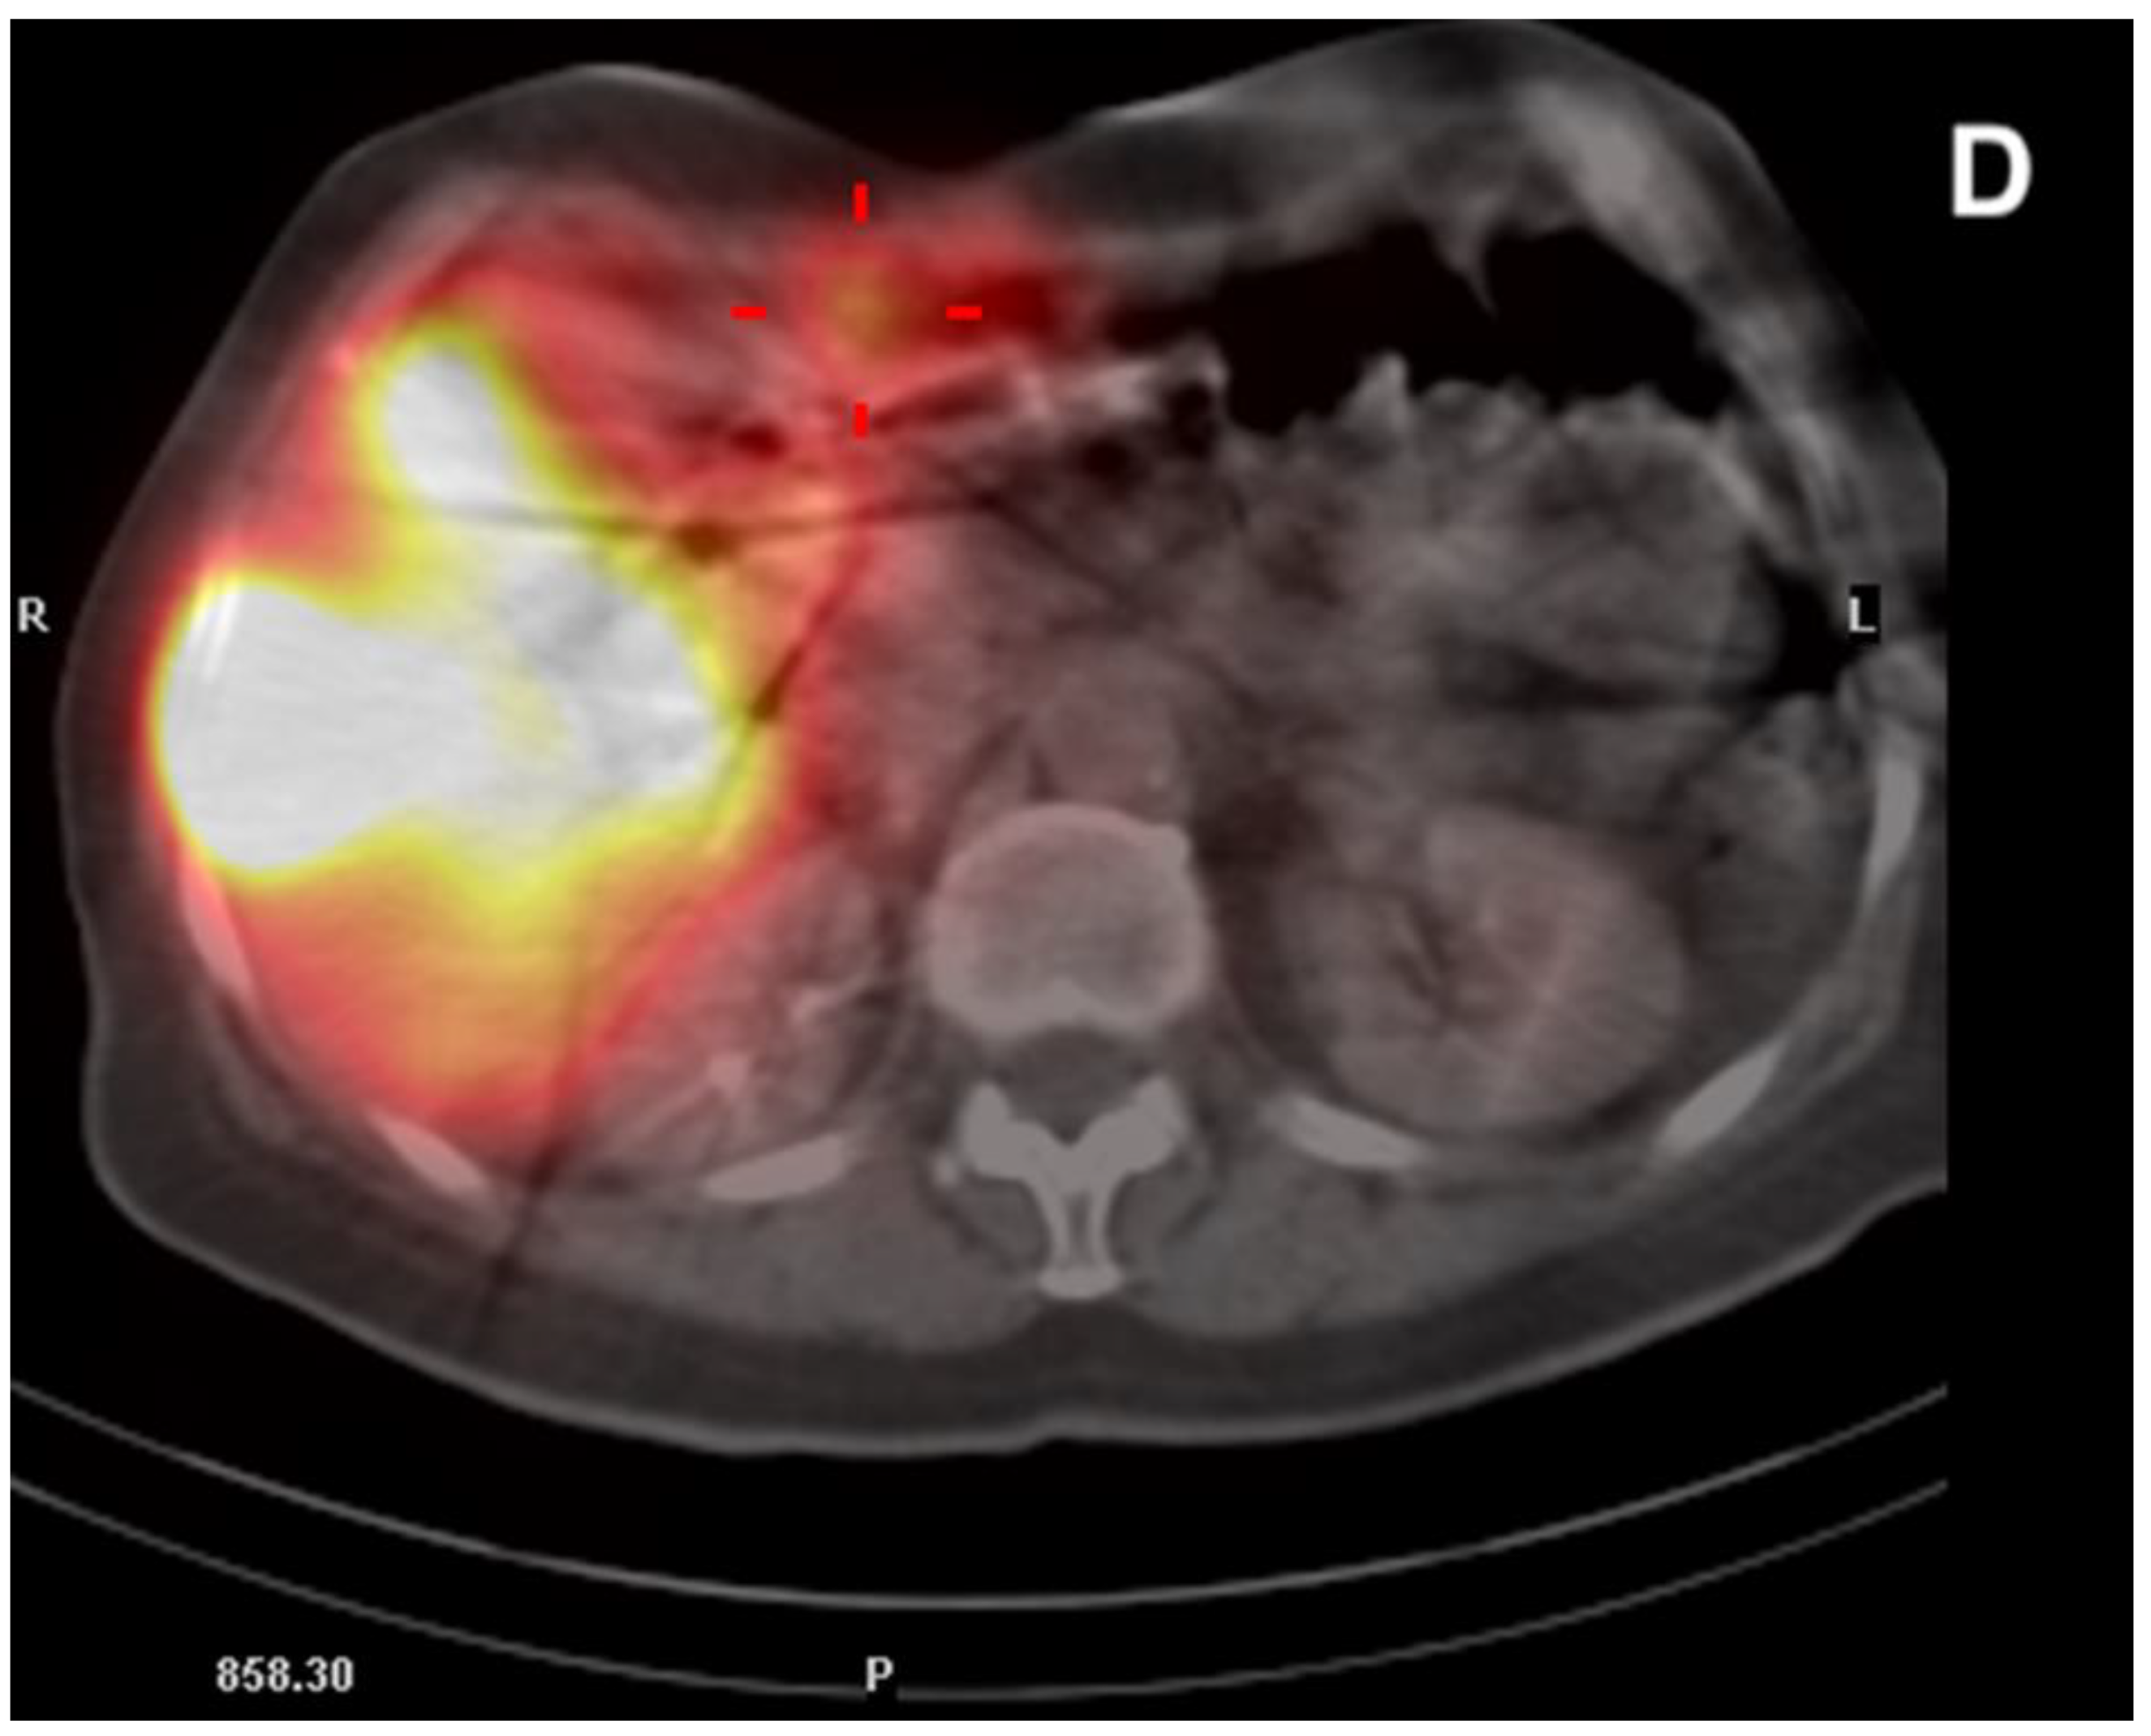

Figure 7.

A computed tomography scan depicting asymptomatic cholecystitis (arrows) after the 90Y leak. The patient did not require surgery and was treated conservatively.